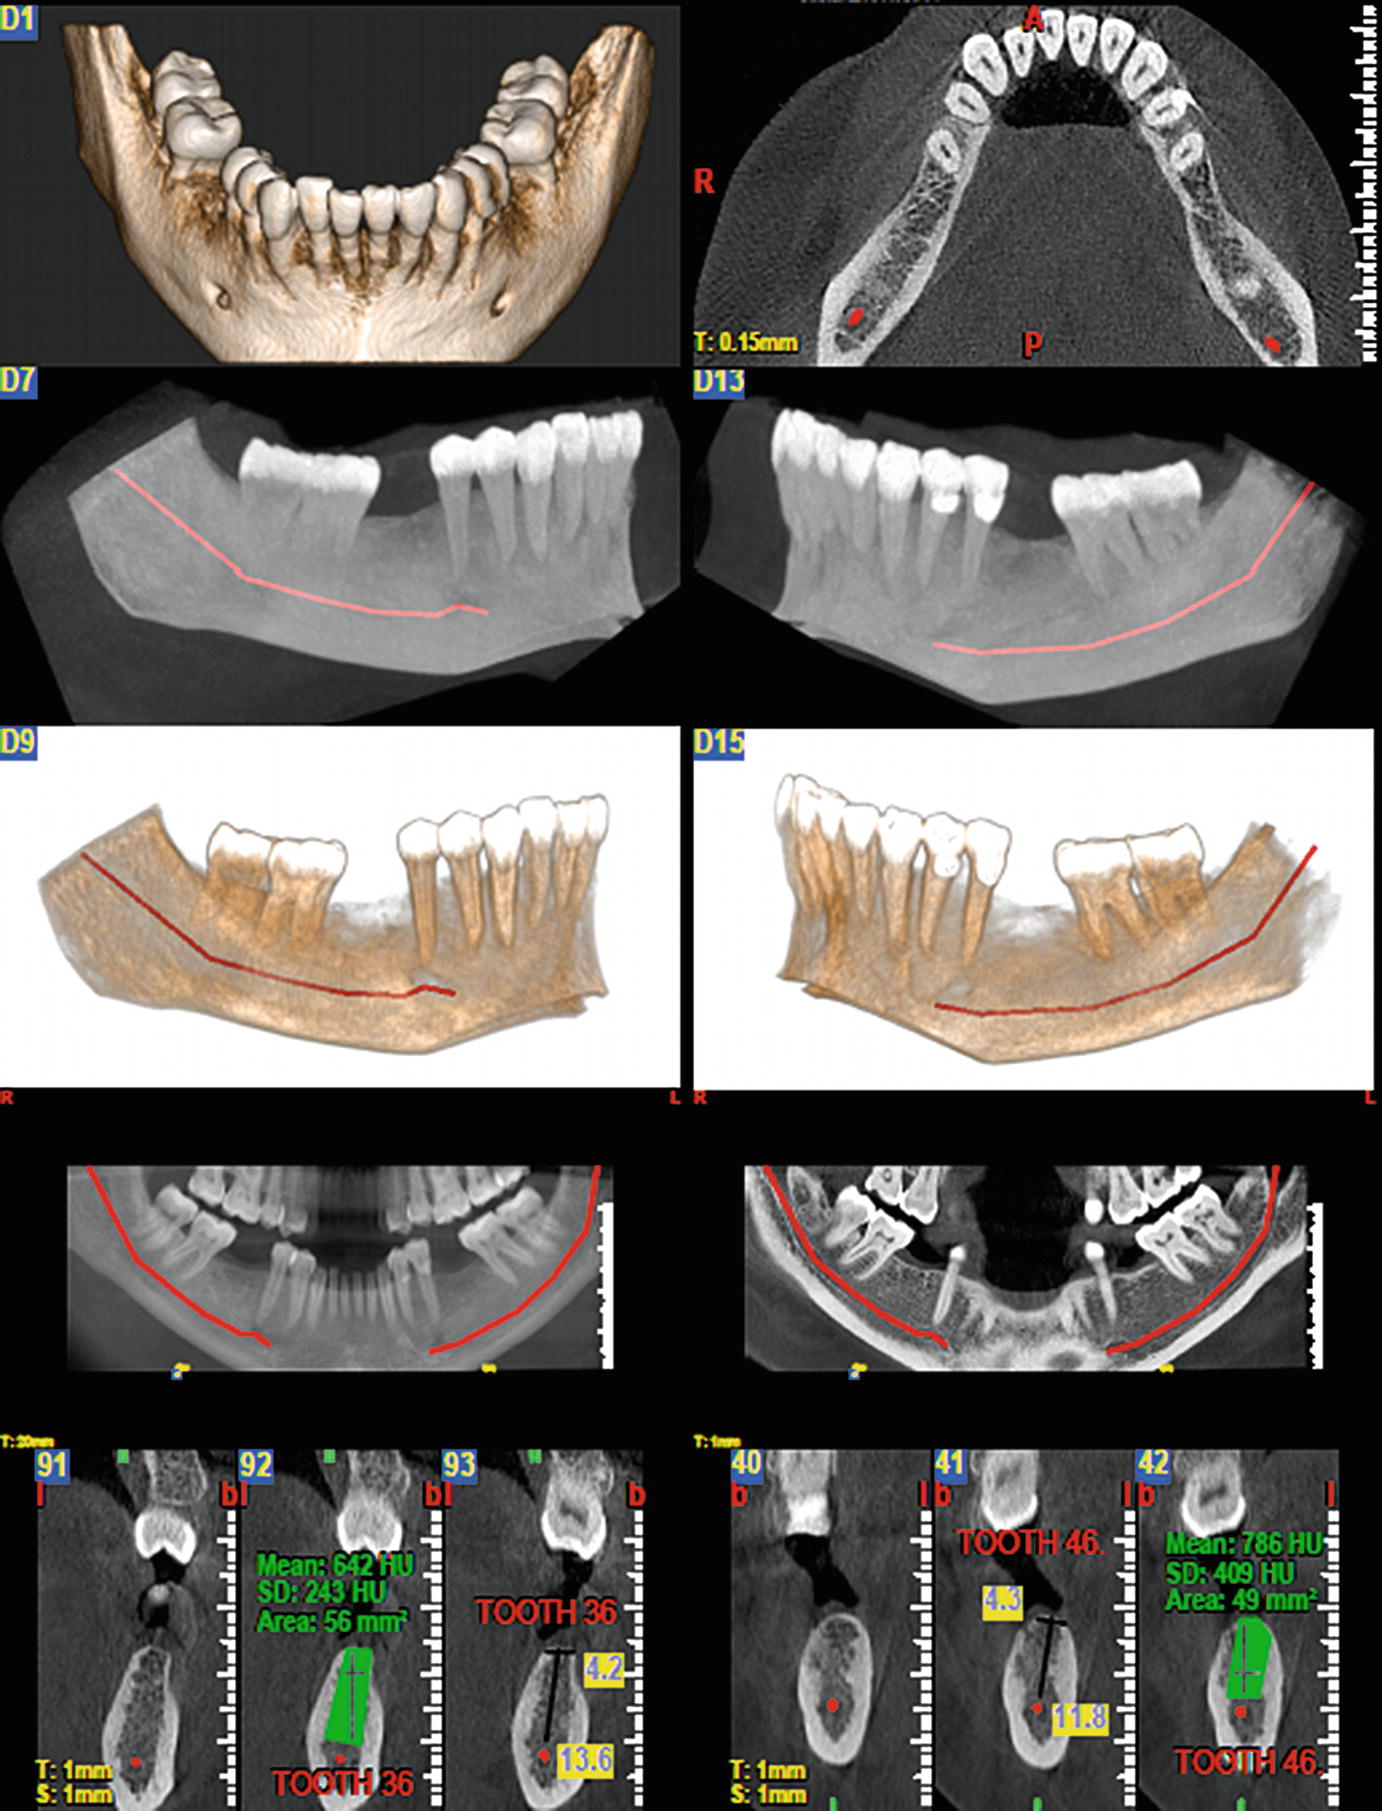

Https Www Birpublications Org Doi Pdf 10 1259 Dmfr 20120271

Diagnostic Imaging Techniques In Oral Diseases Springerlink